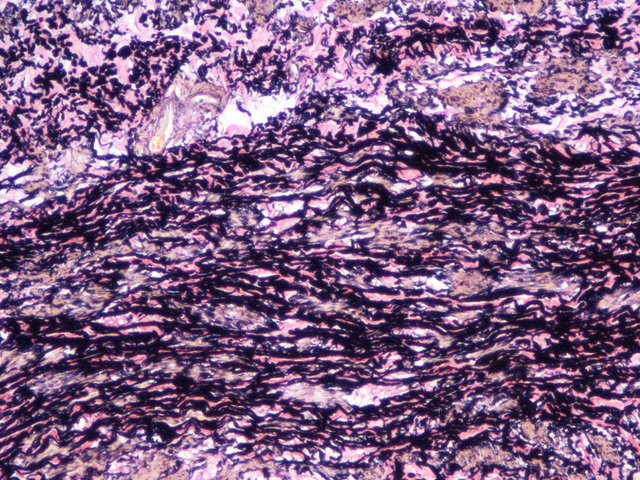

EVG染色样片参考:

弹性纤维呈蓝黑色;胶原纤维呈红色;背景呈淡黄色。

- 可用于区别正常的动脉和静脉以及观察动脉有病变时血管壁各层的情况,如动脉粥样硬化时的各类变化。

- 可用于区别观察各种疾病对弹性纤维的影响及变化,如原发性或继发性高血压可见主动脉弹力纤维增生,老年弹力纤 维增多症。心内膜弹力纤维增生症常都可见到弹力纤维断裂,梅毒性主动脉炎和皮肤的环状肉芽肿,动脉粥样硬化均可见到 裂解,崩解的弹力纤维。